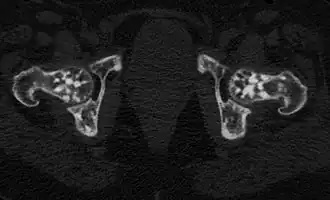

Проявления остеопойкилии в костях таза и головках бедренных костей (компьютерная томограмма).

Заболевание является системным, проявляется очагами остеосклероза округлой и овальной формы, как правило приблизительно одинакового калибра, от 2 мм до 20 мм. Очаги могут располагаться практически во всех костях, однако наиболее часто выявляются в коротких костях запястья и предплюсны, метафизах и эпифизах длинных трубчатых костей (плечевых, бедренных) при интактности их диафизов[6].